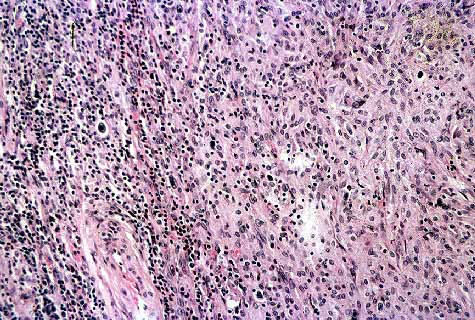

Fig 11.-Histologia perteneciente a área de transición entre aspecto de LH y pseudosarcoma. H&EX20.

Fig 12.- Aspecto con abundantes células de aspecto de fibroblastos, entre ellas observamos algunas células de H.H&EX20.

Fig 14.- Aspecto histologico en que el linfoma presenta un patrona esteriforme que semeja un FHM. H&EX40.